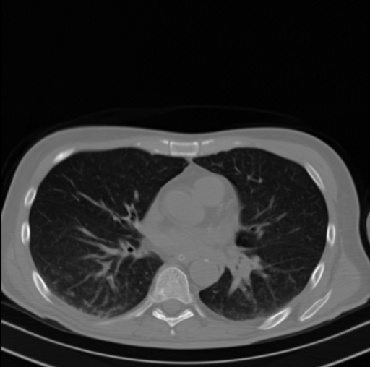

Early and reliable COVID-19 diagnosis based on chest 3-D CT scans can assist medical specialists in vital circumstances. Deep learning methodologies constitute a main approach for chest CT scan analysis and disease prediction. However, large annotated databases are necessary for developing deep learning models that are able to provide COVID-19 diagnosis across various medical environments in different countries. Due to privacy issues, publicly available COVID-19 CT datasets are highly difficult to obtain, which hinders the research and development of AI-enabled diagnosis methods of COVID-19 based on CT scans. In this paper we present the COV19-CT-DB database which is annotated for COVID-19, consisting of about 5,000 3-D CT scans, We have split the database in training, validation and test datasets. The former two datasets can be used for training and validation of machine learning models, while the latter will be used for evaluation of the developed models. We also present a deep learning approach, based on a CNN-RNN network and report its performance on the COVID19-CT-DB database.